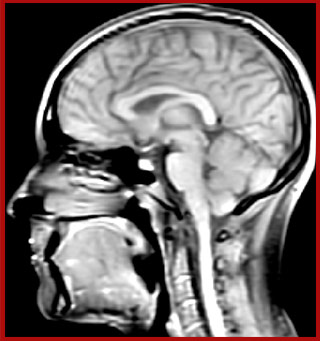

Multiple sclerosis or MS is a neurodegenerative disease that is characterized by myelin degradation, resulting in cognitive and motor deficits. According to Dr. Shannon Kolind, MR imaging for diagnosis and monitoring of MS is moving to higher field strength and using more 3D sequences, as reflected in the CMSC guidelines [1-3].

“In addition to traditional imaging like FLAIR for lesion identification, we see a real push towards techniques that weren’t normally required for MS, including good highresolution 3D T1 weighted images to do volumetrics. We’ve also started looking at spinal cord imaging again, since techniques have improved in terms of acquisition and analysis. Another important technique is susceptibility weighted imaging (SWI), particularly if we are looking for central veins in lesions, which is extremely helpful for diagnosis.”